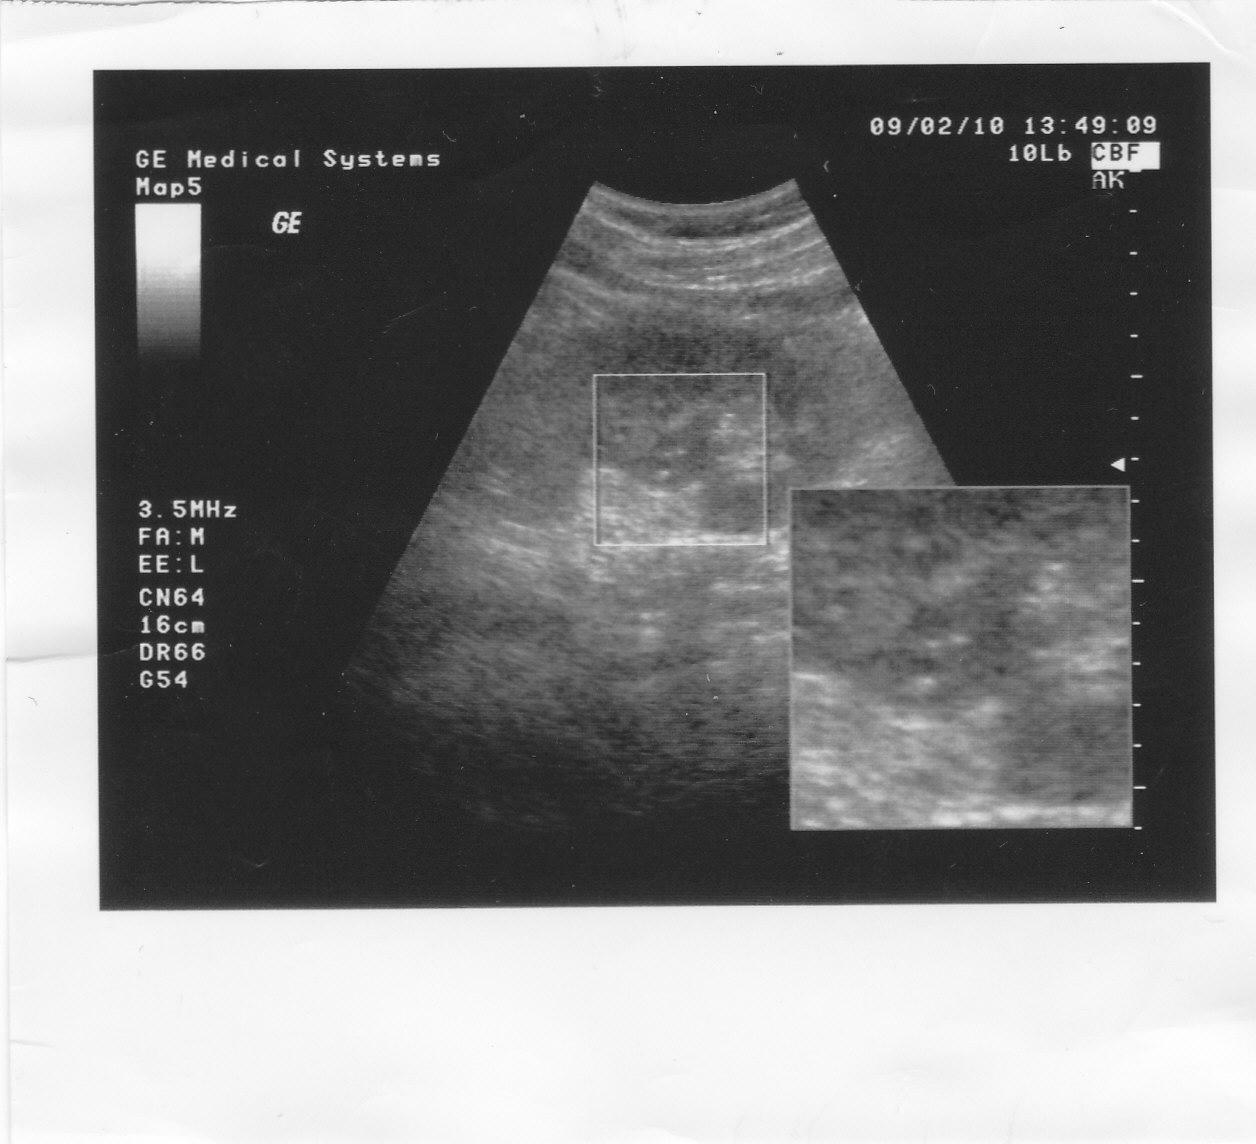

А в 2010 году на снимке видно что то в правой, не оперированой почке.Анализы все в норме.

Отправляю снимки УЗИ.